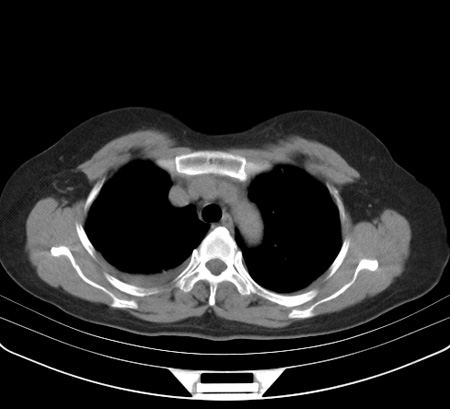

以下是引用余辉在2009-2-19 20:10:00的发言:[br]多考虑急性感染性病变,右中叶尚可见多枚小斑片状影,多为化脓性肺炎,双侧胸腔积液

以下是引用随光逐影在2009-2-19 20:33:00的发言:[br]1)考虑右肺炎症;建议抗炎治疗后复查。2)双侧胸腔积液(以右侧为甚)。

以下是引用花凤凰在2009-2-19 20:46:00的发言:[br]病人有发热,胸痛急性起病,主要病变位于右肺中叶外侧段,呈楔行改变,位于外带胸膜下,考虑为肺梗塞可能!!!!!!!!!!!!!!!!!!!!!!!!!!!!!!!!!!!